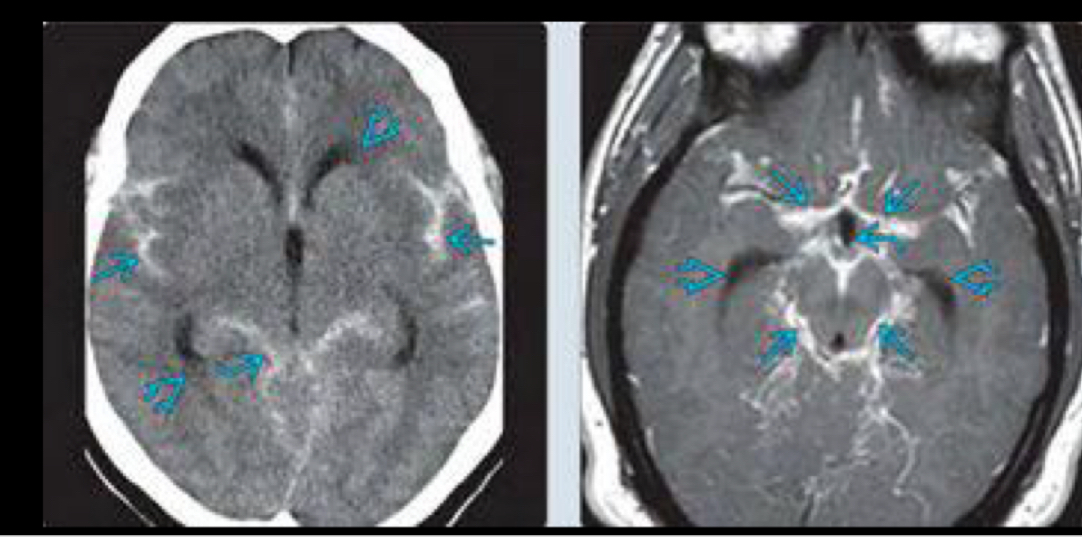

extra ventricular

en la comunicante la obstrucción del flujo del LCR es a nivel de

A

cisternas basales o espacio subaracnoideo

causa mas comun de la comunicante

HAS

otras causas de la comunicante

meningitis supurativas

Exudados inflamatorios neoplasicos